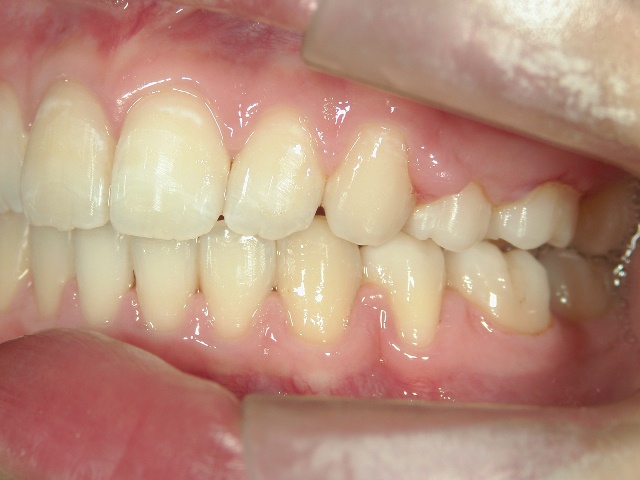

矯正歯科 治療前